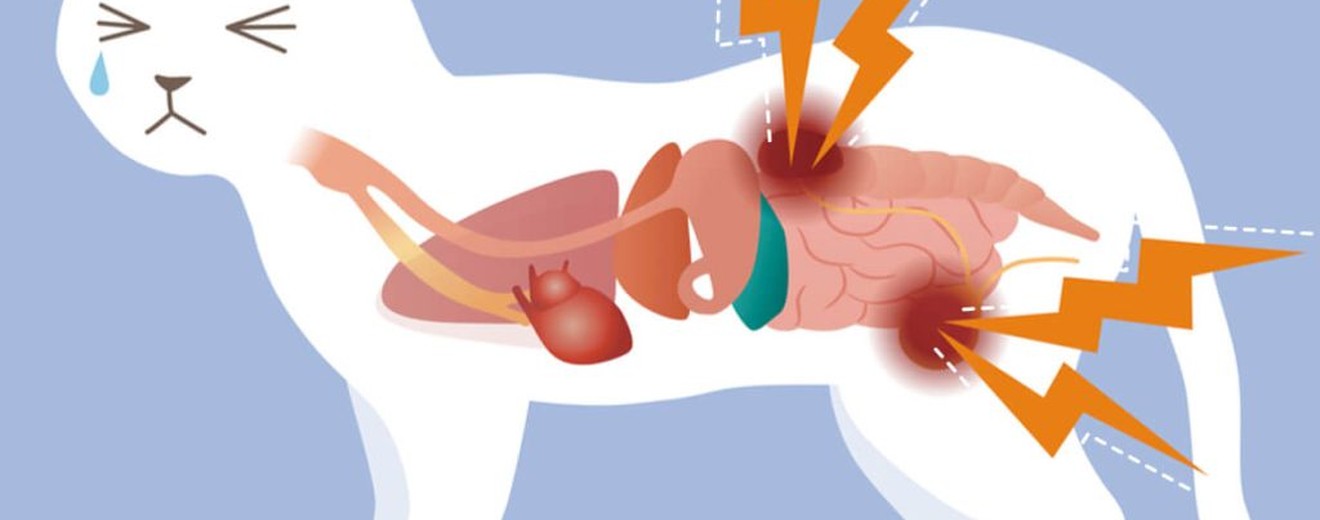

Böbrekler, vücudun toksinleri atması, sıvı dengesi ve hormon üretei için kritik organlardır. Böbrek fonksiyonu azaldığında, toksinler kanda birikir ve ciddi sağlık sorunlarına yol açar. Erken müdahale, hastalığın ilerlemesini yavaşlate ve kedinizin yaşam kalitesini artırır.

Kedilerde böbrek hastalığının erken belirtileri arasında aşırı su tüketimi, sık idrara çıkma, iştah kaybı, kilo kaybı ve halsizlik yer alır. İlerleyen evrelerde kusma, ağızda amonyak kokusu, diş eti ülserleri ve tüy kalitesinde bozulma görülür. Bu belirtiler fark edildiğinde, vakit kaybetmeden veterinere başvurulmalıdır.

Tansiyon ölçümü de önemlidir; böbrek hastalığı olan kedilerde yüksek tansiyon sık görülür ve böbrek hasarını ilerletir. Ultrason ve röntgen, böbreklerin boyutunu ve yapısını değerlendirir; kistler, taşlar veya tümörler tespit edilebilir.